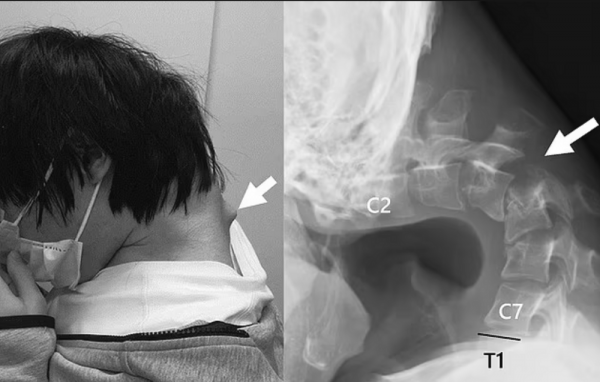

25-летний японец настолько любил играть в игры на телефоне, что практически всё свое время, не поднимая головы, прокачивал свои скилы. В результате продолжительного сидения в позе креветки у него произошла деформация шейного отдела позвоночника.

Парняга потерял возможность поднять голову, не мог нормально есть и прилично сбросил в весе. Когда ситуация уже практически достигла своего апогея, он все же решил обратиться к врачам, те знатно от увиденного удивились. Сначала медики пытались исправить синдром опущенной головы с помощью воротников - медицинских приспособлений, которые надеваются на шею и поддерживают и стабилизируют голову.

Однако, поскольку пациент жаловался на онемение при ношении устройств, данное лечение было прекращено. Решили проблему сурово, провели парочку операций, удалили лишнее, вкрутили ему в шею ряд винтов и металлических стержней, чтобы исправить осанку.